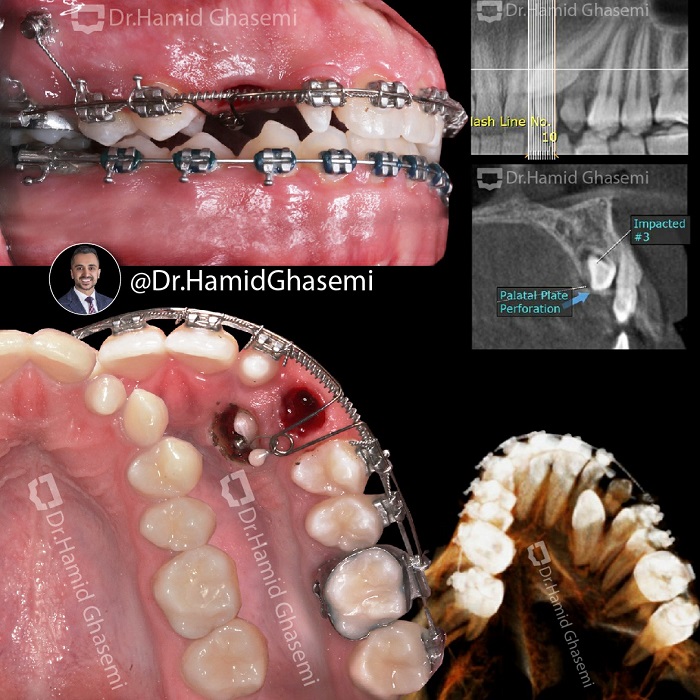

ارتودنسی دندان نهفته؛ راهحلی برای درمان مشکلات پنهان دندانها10 آذر 1403 - 6:20 ب.ظ